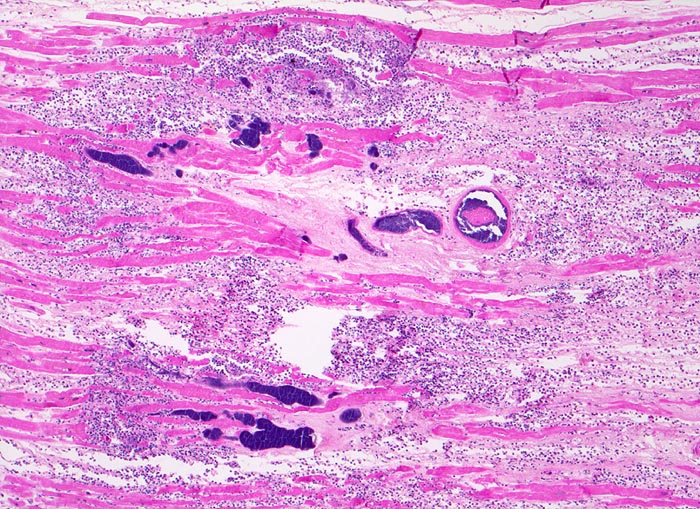

septisch bakterielle Myokarditis (septikopyämische Myokarditis)

Das nekrotische hypereosinophile Myokard wird infiltriert von neutrophilen Granulozyten. Die unregelmässig begrenzten blauen Flecken entsprechen Bakterienhaufen, welche teilweise intravaskulär lokalisiert sind.

Patient mit bakterieller Staphylokokken-Endokarditis der Aortenklappe bei bekanntem intravenösem Drogenabusus.

Dunkelblau in der HE Färbung sind: Bakterien, Kerne (hier der neutrophilen Granulozyten) und Kalk (nicht auf diesem Bild)